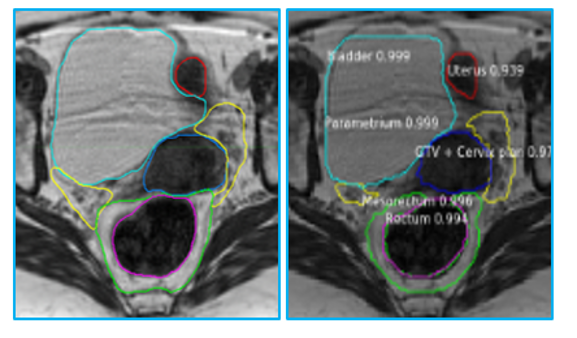

The success of radiation therapy is critically dependent on how accurately and precisely we can detect the location of tumors and characterize their aggressiveness. Over the last 12 years of continuous extramural funding, we have developed advanced imaging approaches to map the location of tumors. Furthermore, using the concept of habitats–areas in the tumor with distinct pathophysiology–we have developed techniques to map tumor heterogeneity. We have designed artificial intelligence (AI) deep learning networks for the automatic identification of tumors and the surrounding organs to maximize the delivery of radiation dose to tumors and to minimize toxicity. Through radiomics, which involves extracting quantitative imaging features in a high-throughput fashion, we have fashioned several models for predicting lesion aggressiveness. These models are informed by genomic signatures for adverse outcome (radiogenomics) and other clinical information. We will further improve risk classification and outcome prediction through the analysis of blood-based markers (such as circulating tumor cells (CTCs), ctDNA, and exosomes) that are early biomarkers of aggressive cancers.

Radiation oncology example of imaging